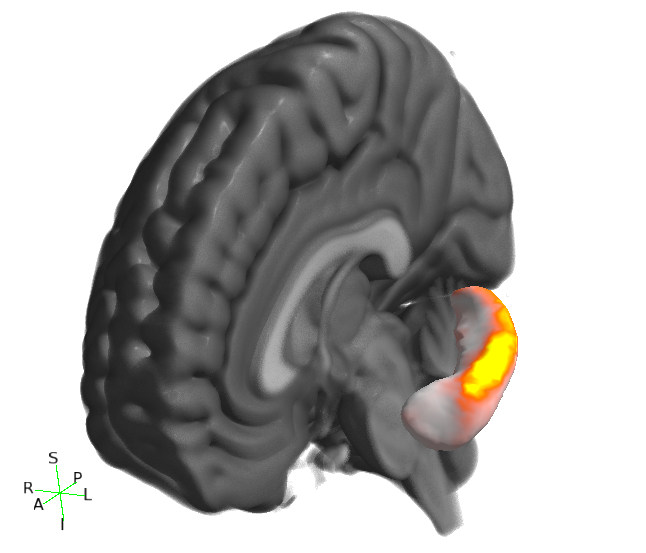

Viewing results in 3D

You can also visualise results in the FSLeyes 3D view. The best results are achieved by using the --saveAverageMesh option when calling first_utils - this will save a group-average surface representation of the structure being analysed, with a file name that ends with _average.vtk (e.g. shape_analysis/con1_dis2_L_Hipp_average.vtk in the first_utils call above).

- Start up FSLeyes, open a 3D view (Views -> 3D View), and add the following as overlays:

- The MNI152 1mm standard template

- The group average surface, e.g.

shape_analysis/con1_dis2_L_Hipp_average.vtk. - the statistic image that you want to visualise, e.g.

con1_dis2_L_Hipp_rand_fstat1.nii.gz. - Select the MNI152 template in the overlay list, open the overlay display dialog (the gear button at top-left), and add some clipping planes to hide portions of the MNI152 as needed. For example, to hide the entire left hemisphere, set the Number of clipping planes to 1, and then set the Clip rotation to 90, and the Clip Z angle to -90.

- Hide the statistic image by clicking on the eye icon next to the image file name in the overlay list.

- Select the group average surface in the overlay list, then select the Tools -> Project image data onto surface menu item. Select the statistic image, and press OK.

- With the surface overlay still selected, adjust the display settings in the overlay display dialog

- Colour set to a desired background colour (dark grey in the example below)

- -ve colour map selected

- First colour map set to Red-yellow

- Second colour map set to Blue-light blue

- Modulate alpha by intensity selected

- Display range and Modulate range adjusted as desired